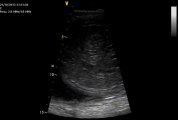

L' Odyssée de sa vie, 5 eme mois

L' Odyssée de sa vie, des interviews de BB directement dans le ventre de sa maman, une série courte d'animation de neuf épisodes.